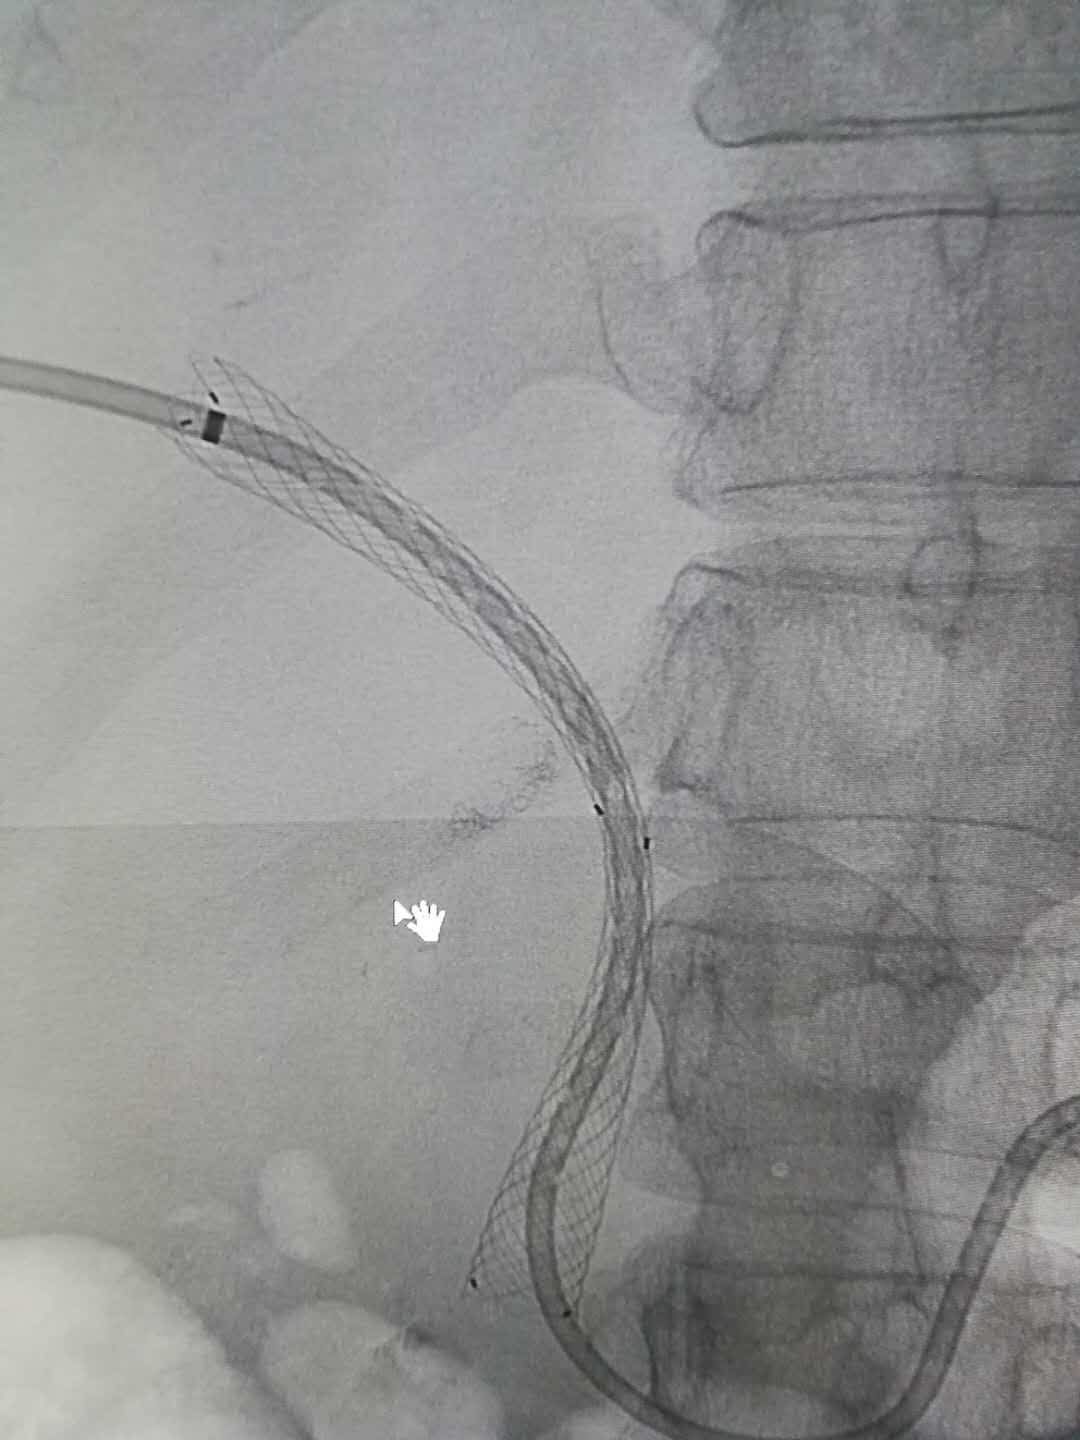

胆道支架植入后造影2018.6.27胃癌术后复发,黄疸.

胃与十二指肠支架置入 写美篇 病例二: 患者因胃癌致幽门梗阻入院

内镜支架置入成功解决胃癌患者梗阻性难题——遵义市消化病临床医学